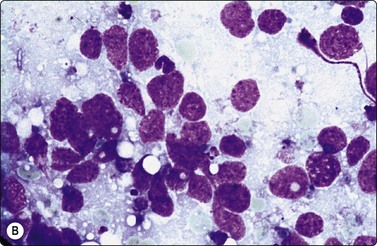

image image

Fig. 5.2 Small cell anaplastic carcinoma

Dispersed malignant cells with dense chromatin, irregular nuclear contour, nuclear molding, inconspicuous nucleoli and cytoplasm; note irregular cytoplasmic (B) and nuclear fragments in the background representing tumor necrosis (A and B) (MGG, HP).